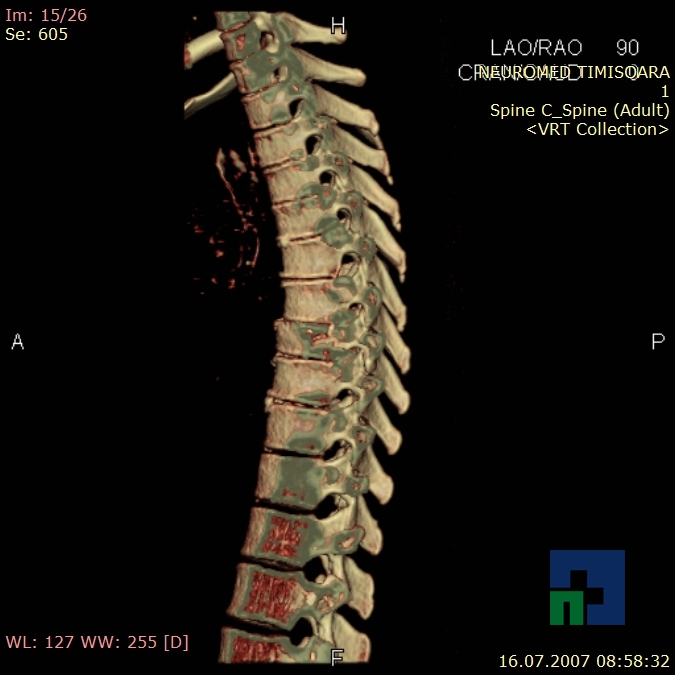

Examinare de rutină cerebrală, nativ și cu substanță de contrast (SDC) pentru diagnosticul:

În cazul traumatismelor cranio-cerebrale:

- Diagnosticul fracturilor:

- Unice

- Multiple

- Cu înfundare

- Complexe cranio-sinusale

- Complexe cranio-etmoidale

- Complexe cranio-orbitare

- Complexe cranio-faciale